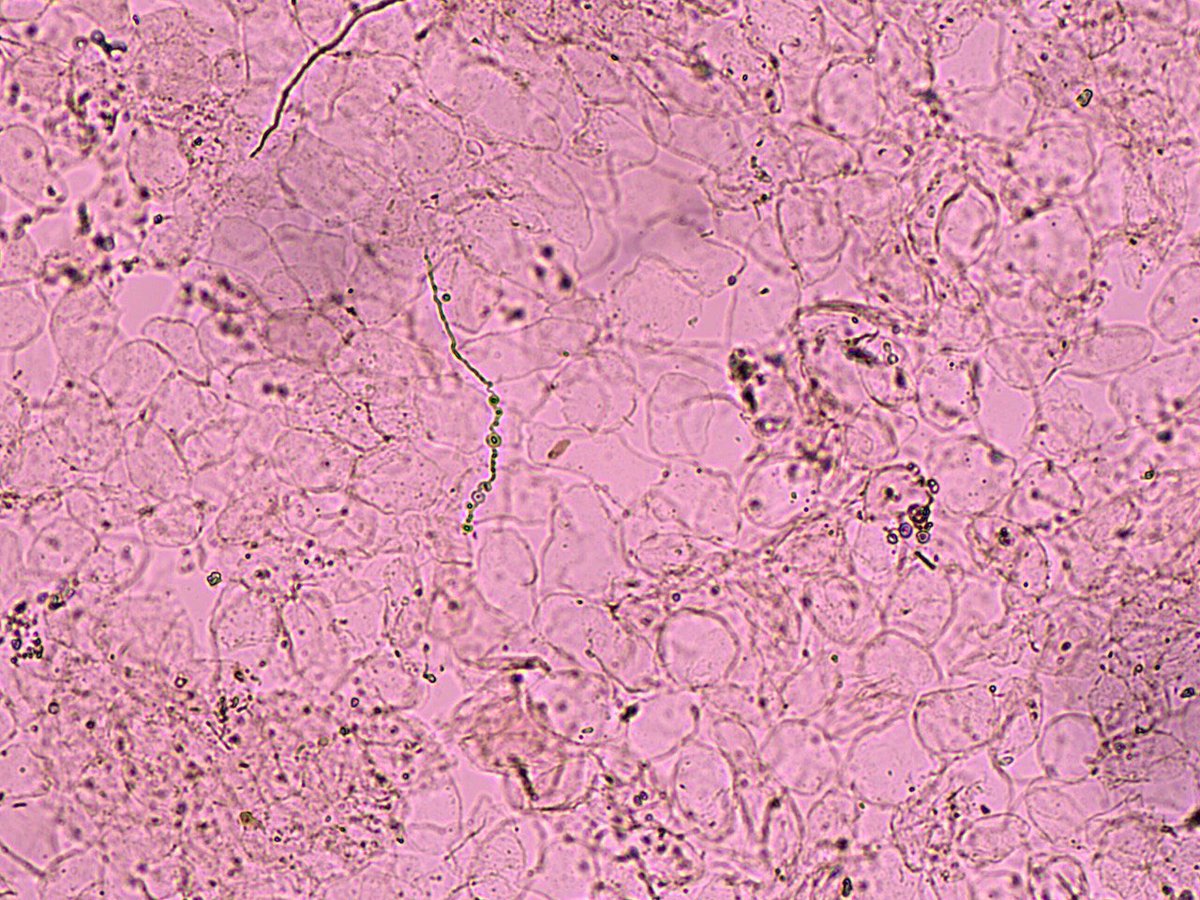

Penfigo foliaceo clínica y citología Wright-Giemsa de célula de Tzanck : células epiteliales acantoliticas redondeadas, con halo perinuclear y condensación periférica del citoplasma .

4

18

81